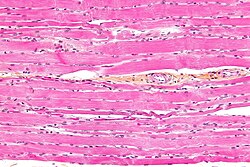

Skeletal muscle. HPS stain. (WC/Nephron)

Microscopic

Features:

• Long fibres with striations - key feature.

• Striations may be difficult to appreciate on cytology.

• Peripheral nuclei.